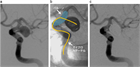

1. 未破裂脳動脈瘤の診断は、カテーテル法によるDSA:digital subtraction angiographyおよびその3次元血管撮影像がゴールドスタンダードである。3D-CTA:3次元ヘリカルコンピュータートモグラフィー、MRA: magnetic resonance angiographyなどは低侵襲な代替え診断法として未破裂脳動脈瘤の診断および治療に用いることが妥当である(推奨度1、J)